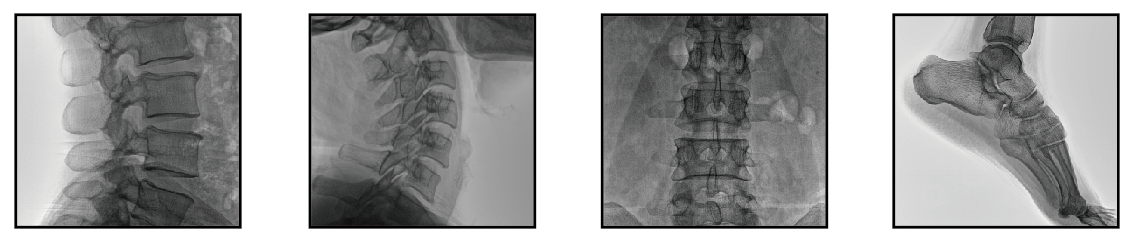

未出生的婴儿被认为比成人或儿童对潜在的有害辐射影响更敏感。在许多检查中,如头部(包括牙齿X光)、胸部和四肢的 X光检查,由于病人的盆腔区域没有暴露在X光射线下,因此对未出生婴儿的剂量会很低。但为了达到更高标准的防护要求,可以在手术过程中着重注意用防护品保护孕妇骨盆区域。